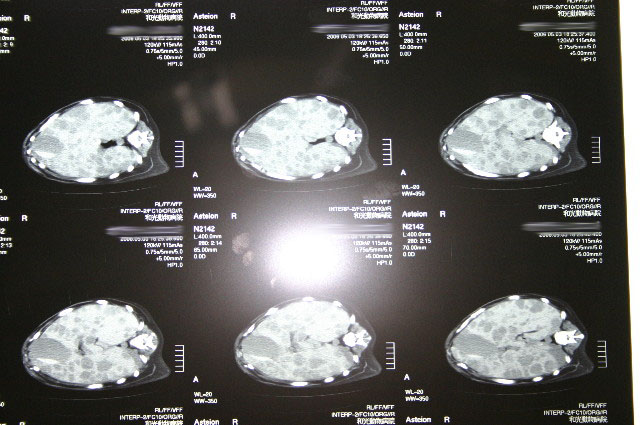

ムーちゃんにとって最善の治療をしてあげるため、状況を正しく把握する為に5月3日に麻酔なしでCTを撮った時には、ガンは肝臓全体に腫瘍が広がり脾臓にも転移していて手も足もでない状態だった。

ほんの2ケ月前にはキレイだった肝臓さんは、たった2ケ月の間のどこかでにっくきガンに冒されてしまい、わずか1ケ月くらいでガンは増殖し肝臓全体を冒していた。